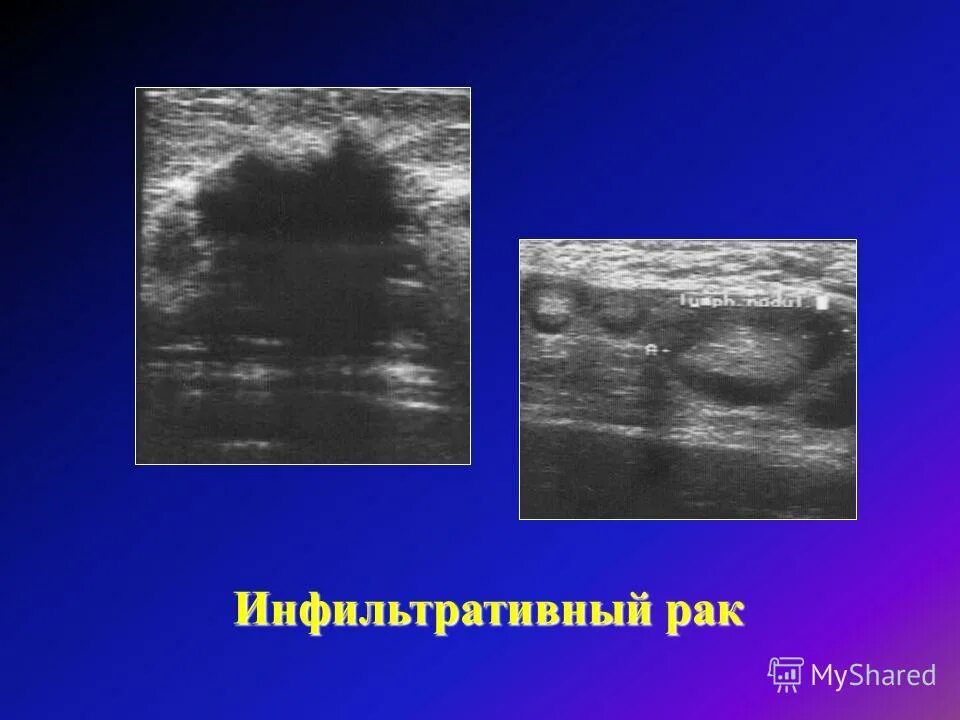

Отечная форма рака молочной